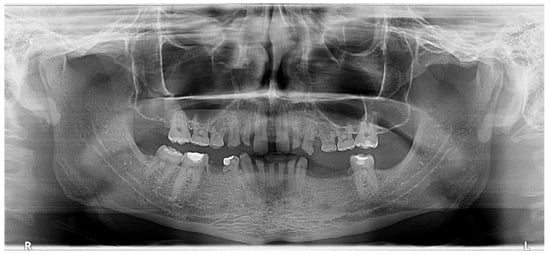

Figure 4.

OPG. Radiographic initial situation of the patient. The radiograph reveals the presence of 7 permanent teeth on the dental arches.

Radiographic examination did not reveal periapical alteration of the present teeth and excluded the diagnosis of dental impaction (Figure 4).